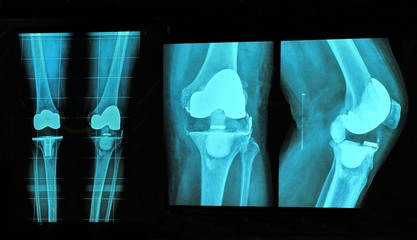

For someone whose knee has become creaky, the method of replacing it with a new, metal-and-plastic version of the joint can be beguiling.

- X-ray examination to assess the total amount of damage caused